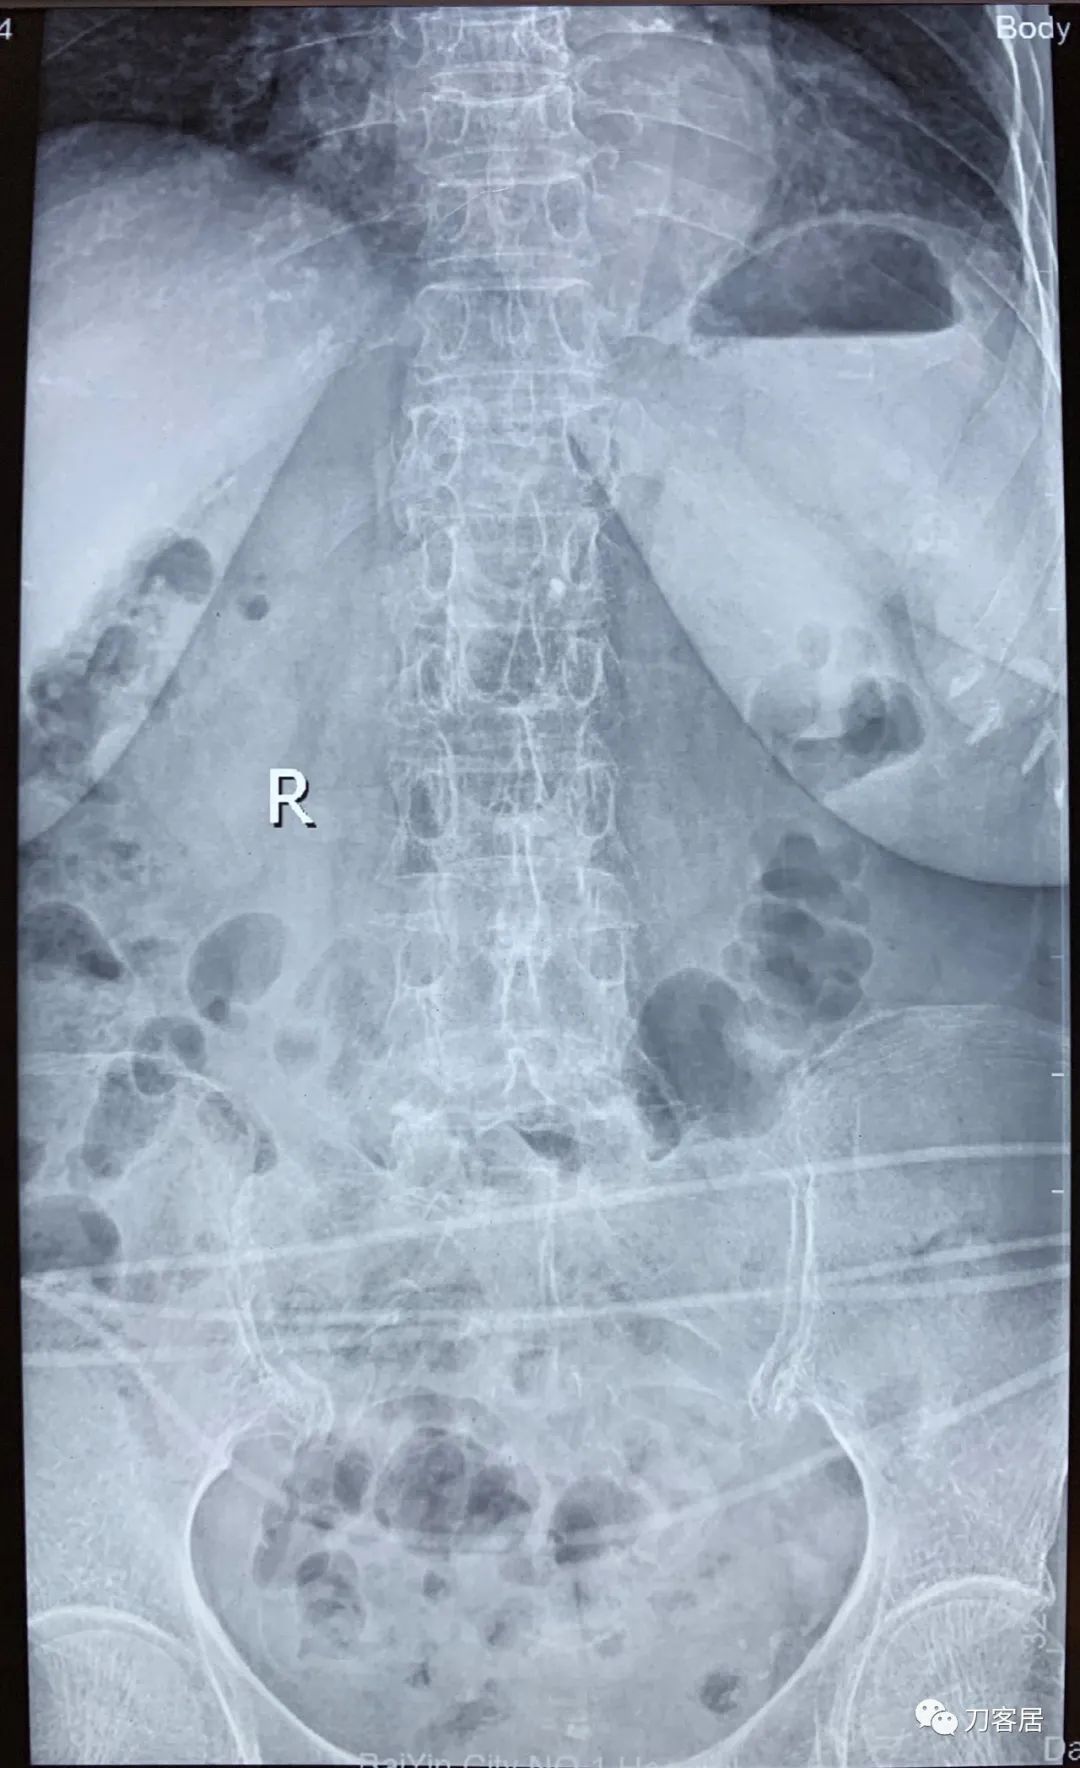

自带影像学资料提示胸椎,腰椎多发脊柱压缩性骨折。

诊断 : 重度骨质疏松症,胸椎、腰椎多发椎体压缩性骨折

图03-20200825腰椎正位X线片